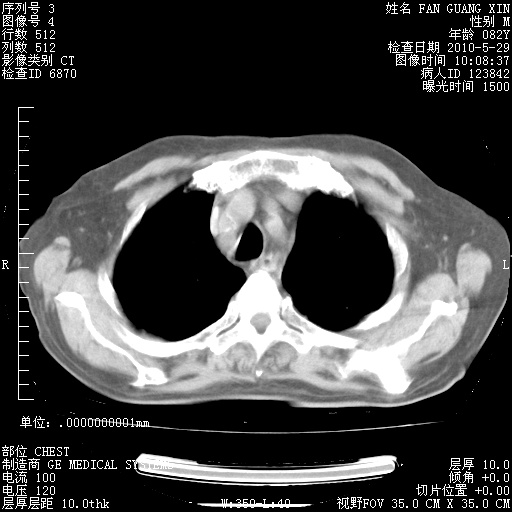

治疗3周后的肺部CT纵隔窗

再治疗10天后的肺部CT

再治疗10天后的肺部CT 纵膈窗

阅读此次胸部CT,肺间质渗出性改变较入院时有吸收。目前从体温、白细胞、中性分叶明显增高,肯定存在细菌感染(发生医院感染哦,若无消化道及泌尿系统等感染的依据,肺部感染可能大)。若你院头孢哌酮舒巴坦钠耐药率较高,同意你的方案,若48小时体温仍高,可考虑使用碳青霉稀类抗菌药物,同时可予超声雾化、注意滴数时加大液体量。白蛋白33.30g/L较低哦,需加强营养等支持治疗。